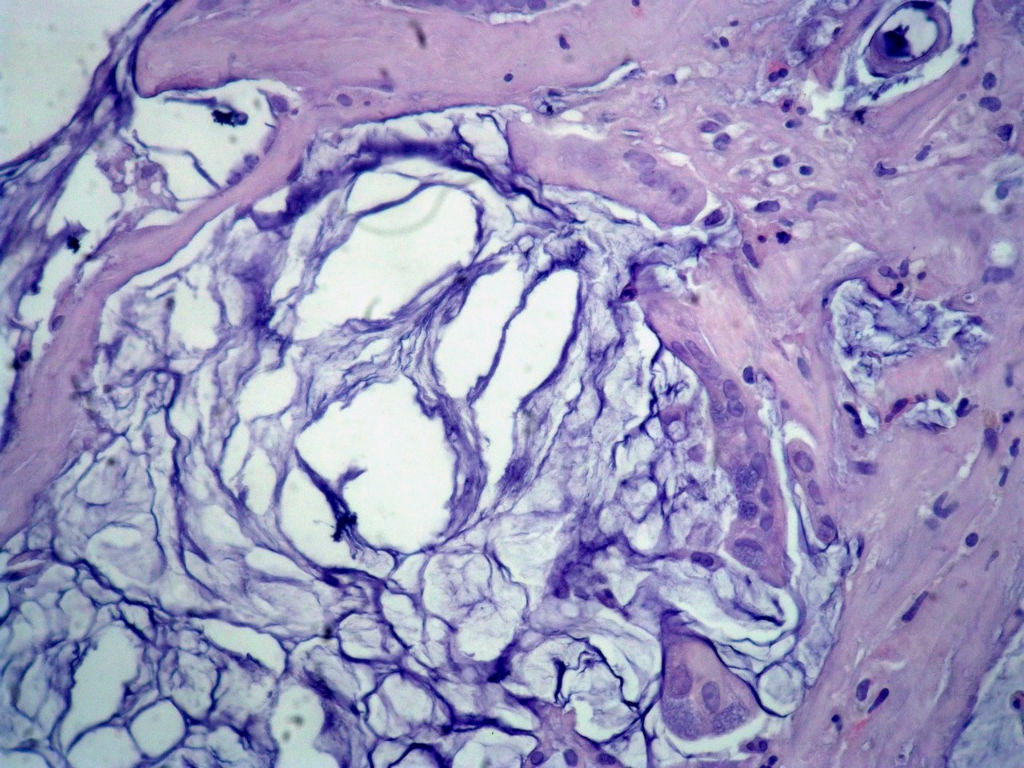

• 女,80岁,阑尾区肿块。图1

图1

送检为不规则组织多块,粘滑,解剖结构辨认不清。术中探查双侧卵巢无异常。

阑尾粘液性肿瘤,癌的可能性大

粘液长在肌层,而且漂浮着可疑上皮细胞,最大可能粘液腺癌。